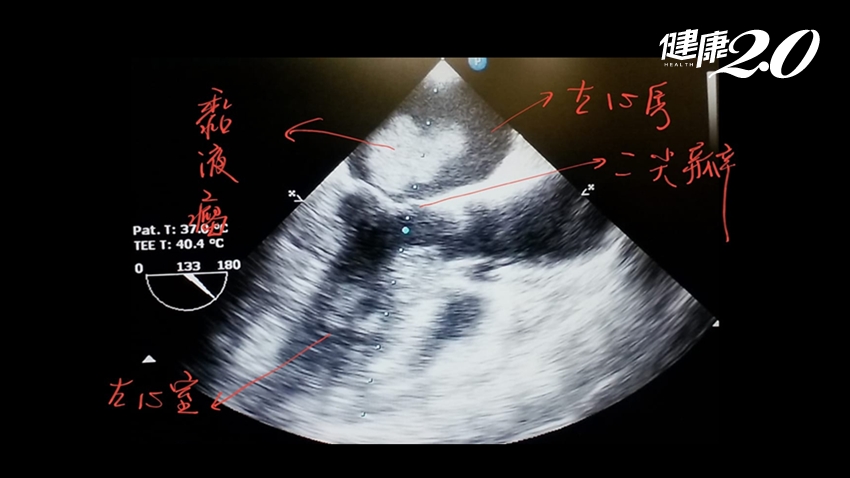

收治個案的門諾醫院心臟外科主任黃振銘指出,該病患的心臟黏液瘤幾乎占滿了左心房,隨著心臟收縮穿過二尖瓣掉入左心室,可能是部份腫瘤的碎片掉出,阻塞大腦血管造成腦中風。

▲婦人心臟黏液瘤碎片阻塞大腦血管造成腦中風。